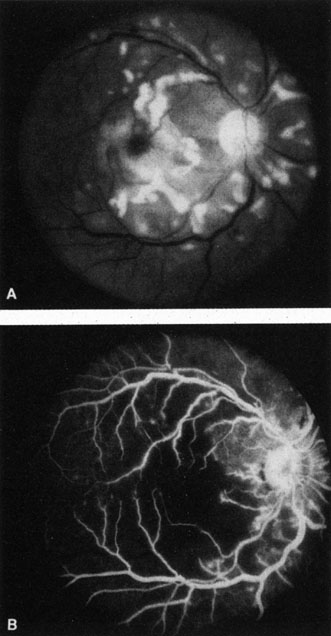

OBSTRUCTION OF A RETINAL ARTERIOLE

Obstruction of a retinal arteriole produces cotton-wool spots, which have also been called white patches or soft exudates (Fig. 7). Cotton-wool spots are caused by focal hypoxia, which obstructs axoplasmic flow, resulting in accumulations of axoplasmic debris in the nerve fiber layers of the retina.142–144 Cotton-wool spots may be either single or multiple. On intravenous fluorescein angiography, they correspond to areas of capillary nonperfusion.6 The patients are often asymptomatic but may experience severe visual loss if the areas of arteriolar obstructions are extensive (Fig. 8).145

Fig. 8. A: Extensive cotton-wool spots and (B) corresponding large areas of vascular nonperfusion in a patient with Purtscher's-like retinopathy associated with systemic lupus erythematosus. The condition was bilateral.

There are multiple causes for cotton-wool spots. Brown and co-workers146 studied 24 consecutive patients who presented with a cotton-wool spot; any patient with known diabetes mellitus was excluded. In this series, 23 of the 24 patients were found to have one or more associated systemic diseases. The disease entities associated with cotton-wool spots are listed in Table 2.